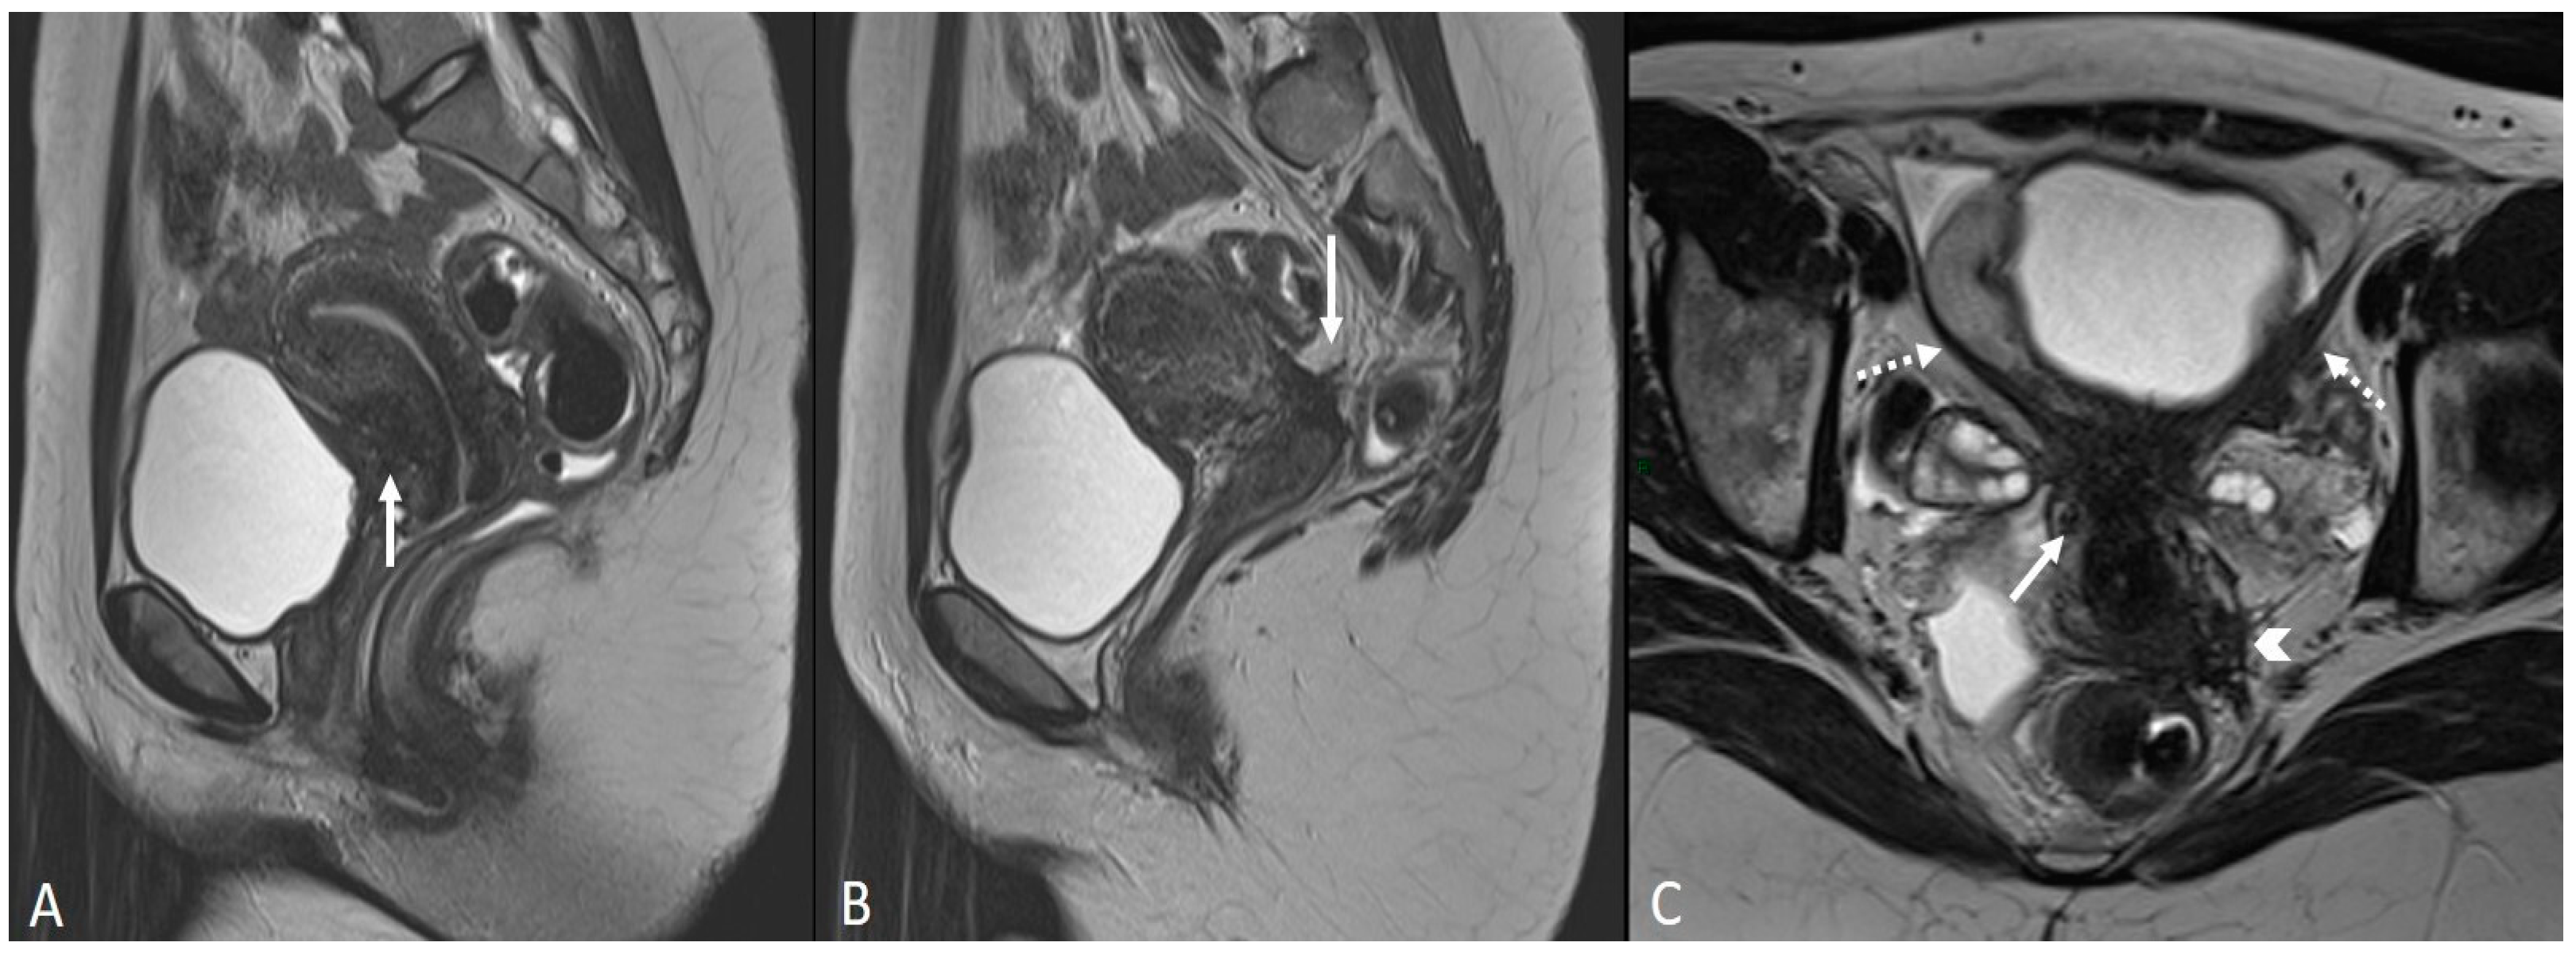

In order to perform a correct evaluation, the bladder must be at a degree of repletion suitable for the correct study of its walls and its lumen: those nodules or masses are responsible for the loss of the normal hypointense signal of the muscularis layer on T2WI. Hemorrhagic content may also be seen as hyperintense foci on T1WI, and it is also possible to observe hyperintense cystic areas on T2WI [7,14] (Figure 1).

Figure 1.

Localization of endometriosis in the vesico-uterine pouch in a 42-year-old female. (A) Sagittal T2WI (black arrow); (B) Sagittal fat-suppressed T1WI (white arrow); (C) Coronal T2WI (black arrow).

In the case of a mural mass protruding into the lumen, mucosal or submucosal edema is well depicted on T2WI [40].